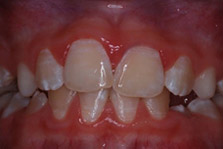

Tooth whitening is suitable for the treatment of mild to moderate fluorosis, and masks the white striae/mottling associated with dental fluorosis by whitening the surrounding tooth structure such that the areas blend in. Enamel microabrasion is achieved using a commercial paste containing a low concentration of hydrochloric acid and an abrasive, or phosphoric acid and pumice, that is repeatedly applied with pressure using a rubber cup and low-speed handpiece.24Donly KJ, O’Neill M, Croll TP. Enamel microabrasion: a microscopic evaluation of the “abrosion effect”. Quintessence Int 1992;23:175-9.,25Pini NIP, Sundfeld-Neto D, Aguiar FHB, Sundfeld RH, Martins LRM, Lovadino JR, Lima DANL. Enamel microabrasion: An overview of clinical and scientific considerations. World J Clin Cases 2015;3(1):34-41. This removes fluorotic/dysmineralized enamel and stains, and creates a dense, glasslike surface that alters the reflection and refraction of light and helps to mask the underlying area.24Donly KJ, O’Neill M, Croll TP. Enamel microabrasion: a microscopic evaluation of the “abrosion effect”. Quintessence Int 1992;23:175-9. (Figure 3) One study found improvements in esthetics and oral health-related quality of life one month after treatment of fluorotic areas with enamel microabrasion with or without subsequent toothwhitening.21Meireles SS, Goettems ML, Castro KS, Sampaio FC, Demarco FF. Dental fluorosis treatment can improve the individuals' OHRQoL? Results from a randomized clinical trial. Braz Dent J 2018;29(2):109-16.

Figure 3. Treatment of dysmineralized enamel with microabrasion

- Initial presentation

- During enamel microabrasion

- Immediately after enamel microabrasion

- After enamel microabrasion

Images courtesy of Dr. Ted Croll